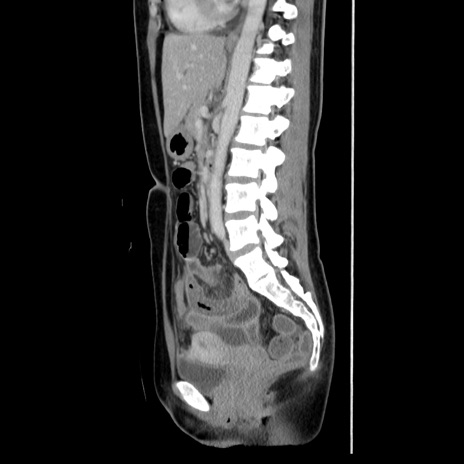

症例39(矢状断像)

CT